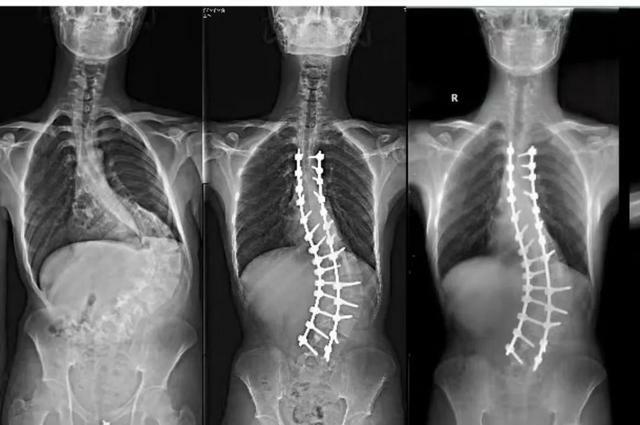

眼前的小伙陽光帥氣,笑容燦爛,腰板挺得筆直,和兩年前脊柱嚴重畸形的他相比,判若兩人。可以說,在遇到王華鋒之前,阿明的人生和畸形的脊柱一樣「扭曲」。

原來,3歲時阿明意外跌進沸水中,腰背部大面積燙傷。後面漫長歲月里,缺乏彈性的瘢痕影響了脊柱正常生長,牽拉限制下,脊柱呈S狀側彎。

半年時間裡,阿明130°側彎漸漸實現了60%修正度,從外觀上幾乎看不出側彎。接下來,每一次複查,王華鋒都感受到阿明的變化,不僅身體更加挺拔,人也自信陽光了,還談了女朋友。